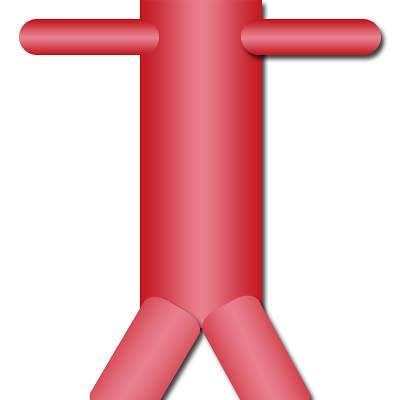

L’aorte est le gros vaisseau qui sort du cœur et qui va successivement donner naissance à tous les autres vaisseaux du corps humain. Lorsqu’elle traverse le diaphragme, elle devient aorte abdominale (après la naissance des artères rénales elle devient aorte abdominale sous-rénale) et finit par se diviser en artères iliaques qui assurent la vascularisation des membres inférieurs.

Aorte abdominale